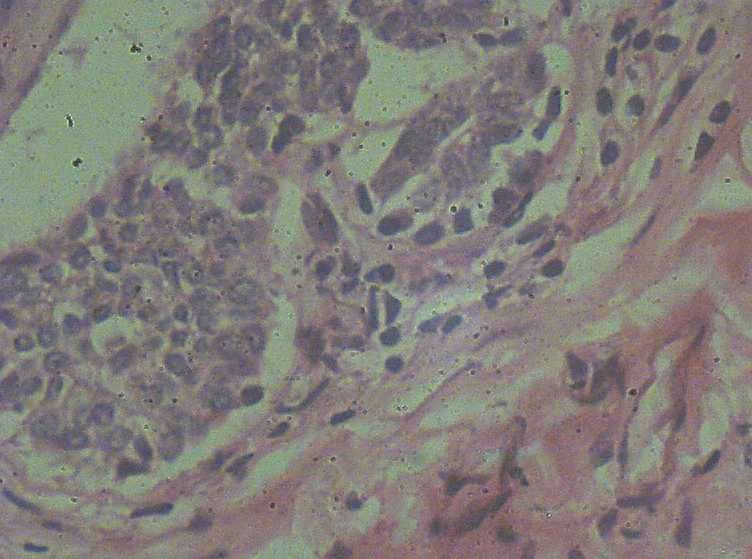

B3774乳腺积乳性包块?

女41岁,左腺包块。肉眼:不整形囊壁样组织,大小2*1.6*0.3CM,壁厚0.1—0.3,未触及结节,未见出血及坏死。

标签:乳腺纤维囊性增生症

似乎有导管扩张、慢性炎细胞浸润、大汗腺化生、普通型导管增生等病变,没有看到囊壁内衬上皮或囊壁结构。

报乳腺增生性腺病伴导管上皮不典型增生。

。图12-16可以看到导管上皮异形增生(导管上皮极向紊乱)